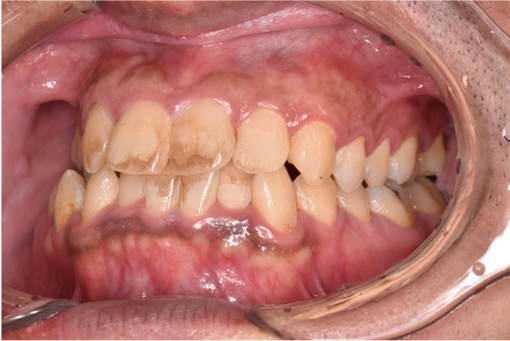

治療前

| カウンセリング・診断結果 | 拝見したところ、ご相談の通り歯面に着色が付着している状態でした。 全顎ステイン(+++) |